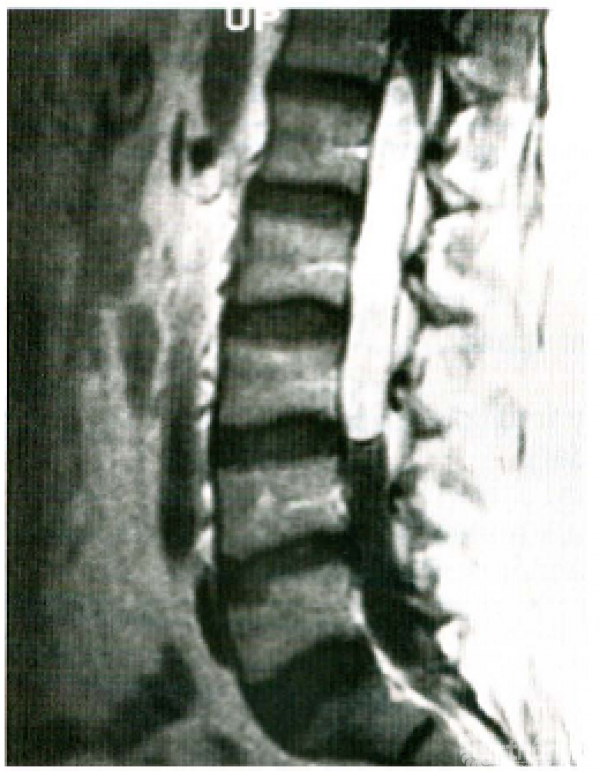

腰痛的鉴别诊断有许多,例如强直性脊柱炎早期阶段,年轻患者表现为不确定的骶骼关节疼痛、轻度臀部和大腿部不适,可被误认为是腰椎间盘突出症。另一个例子就是表现为坐骨神经痛的患者,不排除脊髓圆锥肿瘤的可能(图1)。腹膜后肿瘤侵袭骶骨或骶丛神经,患者亦可以表现为典型的坐骨神经痛,可误诊为腰椎间盘突出症。腹腔内存在病变的患者出现背部牵涉痛并非罕见。为避免误诊,应时常询问自己第二个问题:需要与之相鉴别的疾病包括哪些?

图1 圆锥肿瘤(神经鞘瘤),钆注射后的T1矢状面MRI图像。1年前未增强扫描时,资深作者(JM)和所有的神经放射学医师均漏诊了此病。在钆增强扫描后很容易发现该病变。